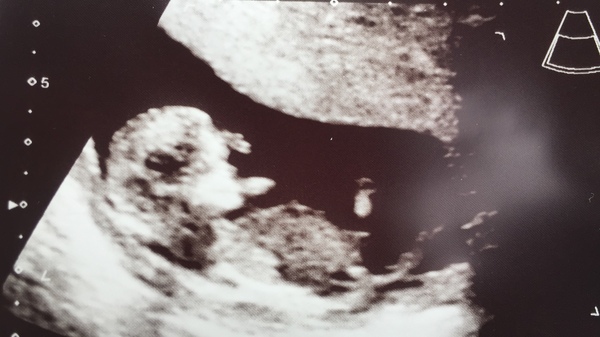

Hi girls. Well I went to the EPU this morning after a bit of bleeding last Thursday and everything is looking ok. Baby is measuring 11+4 perfect for my dates and was wiggling so so much. I cried.

I’ve got my 12 week Scan this Thursday morning and I can’t wait now.

Great news magical! Lovely pic.

If anyone wants to have a go at the nub theory I’m game. I’ve already been obsessing over it 😂

Yayyyy @MagicalCreatures lovely scan!! And yay it's time for nub theory... I actually think girl looking at your photo but will revise my guess after your 12 week scan!

Thanks @kaytees I’m still convinced it’s a boy but yes, I think another 3 days and it might be even clearer at the 12 week mark.

Oooh have a guess at my bub's nub!! Eek!!

@Cakelaur What an amazing picture 😊 So exciting! I'm going to guess boy, but to be fair I'm normally wrong, haha!